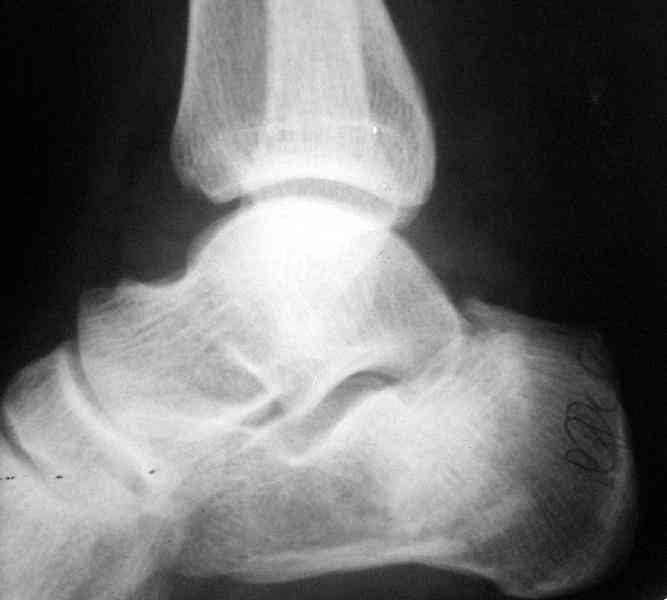

Re: Перелом пяточной кости

послал А.П.Ким 09 Октябрь 2007, 09:41

Открытый и закрытый способы лечения.